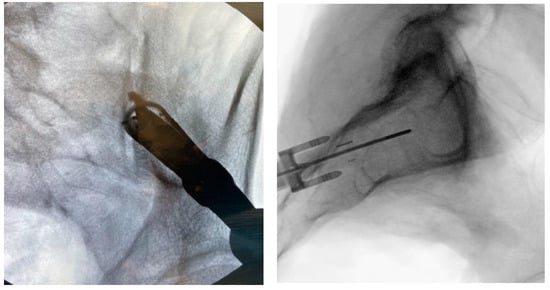

3.3.5. Tissue Dilation

3.3.6. Implant Preparation

3.3.7. Docking Washer Introduction